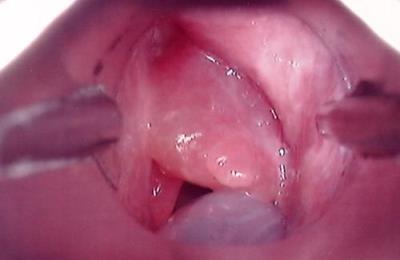

Опухоли могут быть как доброкачественными, так и злокачественными. При первом типе обычно хирургический путь лечения помогает восстановить здоровье и дыхательные, а также голосовые функции, и рецидивы появляются очень редко. А вот рак гортани – это очень опасная патология.

Симптомы рака:

- болит в гортани, особенно при глотании;

- глотание затруднено;

- голос пациента изменен.

Если данные симптомы длятся более 14 дней, то необходимо немедленно обращаться за медицинской помощью. В большинстве случаев на первой стадии рака гортани симптомы отсутствуют. Потом появляются новые признаки: хронический кашель, режущие боли, боли в ушах (ухе), потеря веса. Опухоль может становиться видна в области кадыка.

Рак имеет пять стадий. На последней из них лечение практически бесполезно. Вообще терапия состоит в лучевой терапии, химиотерапии и оперативном вмешательстве. Лучевую терапию проводят курсом около восьми недель.